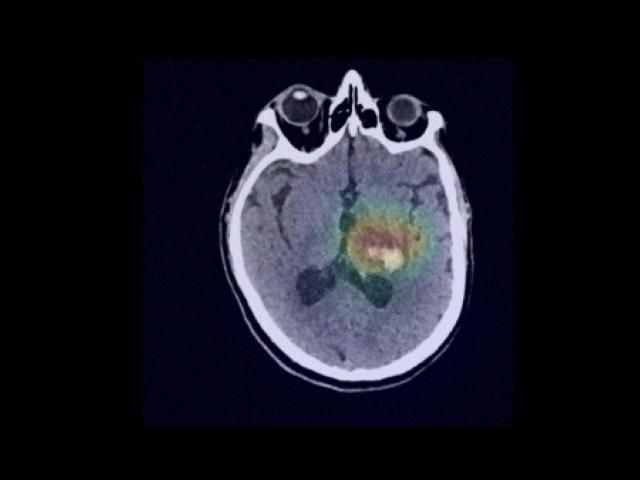

Sample Gallery